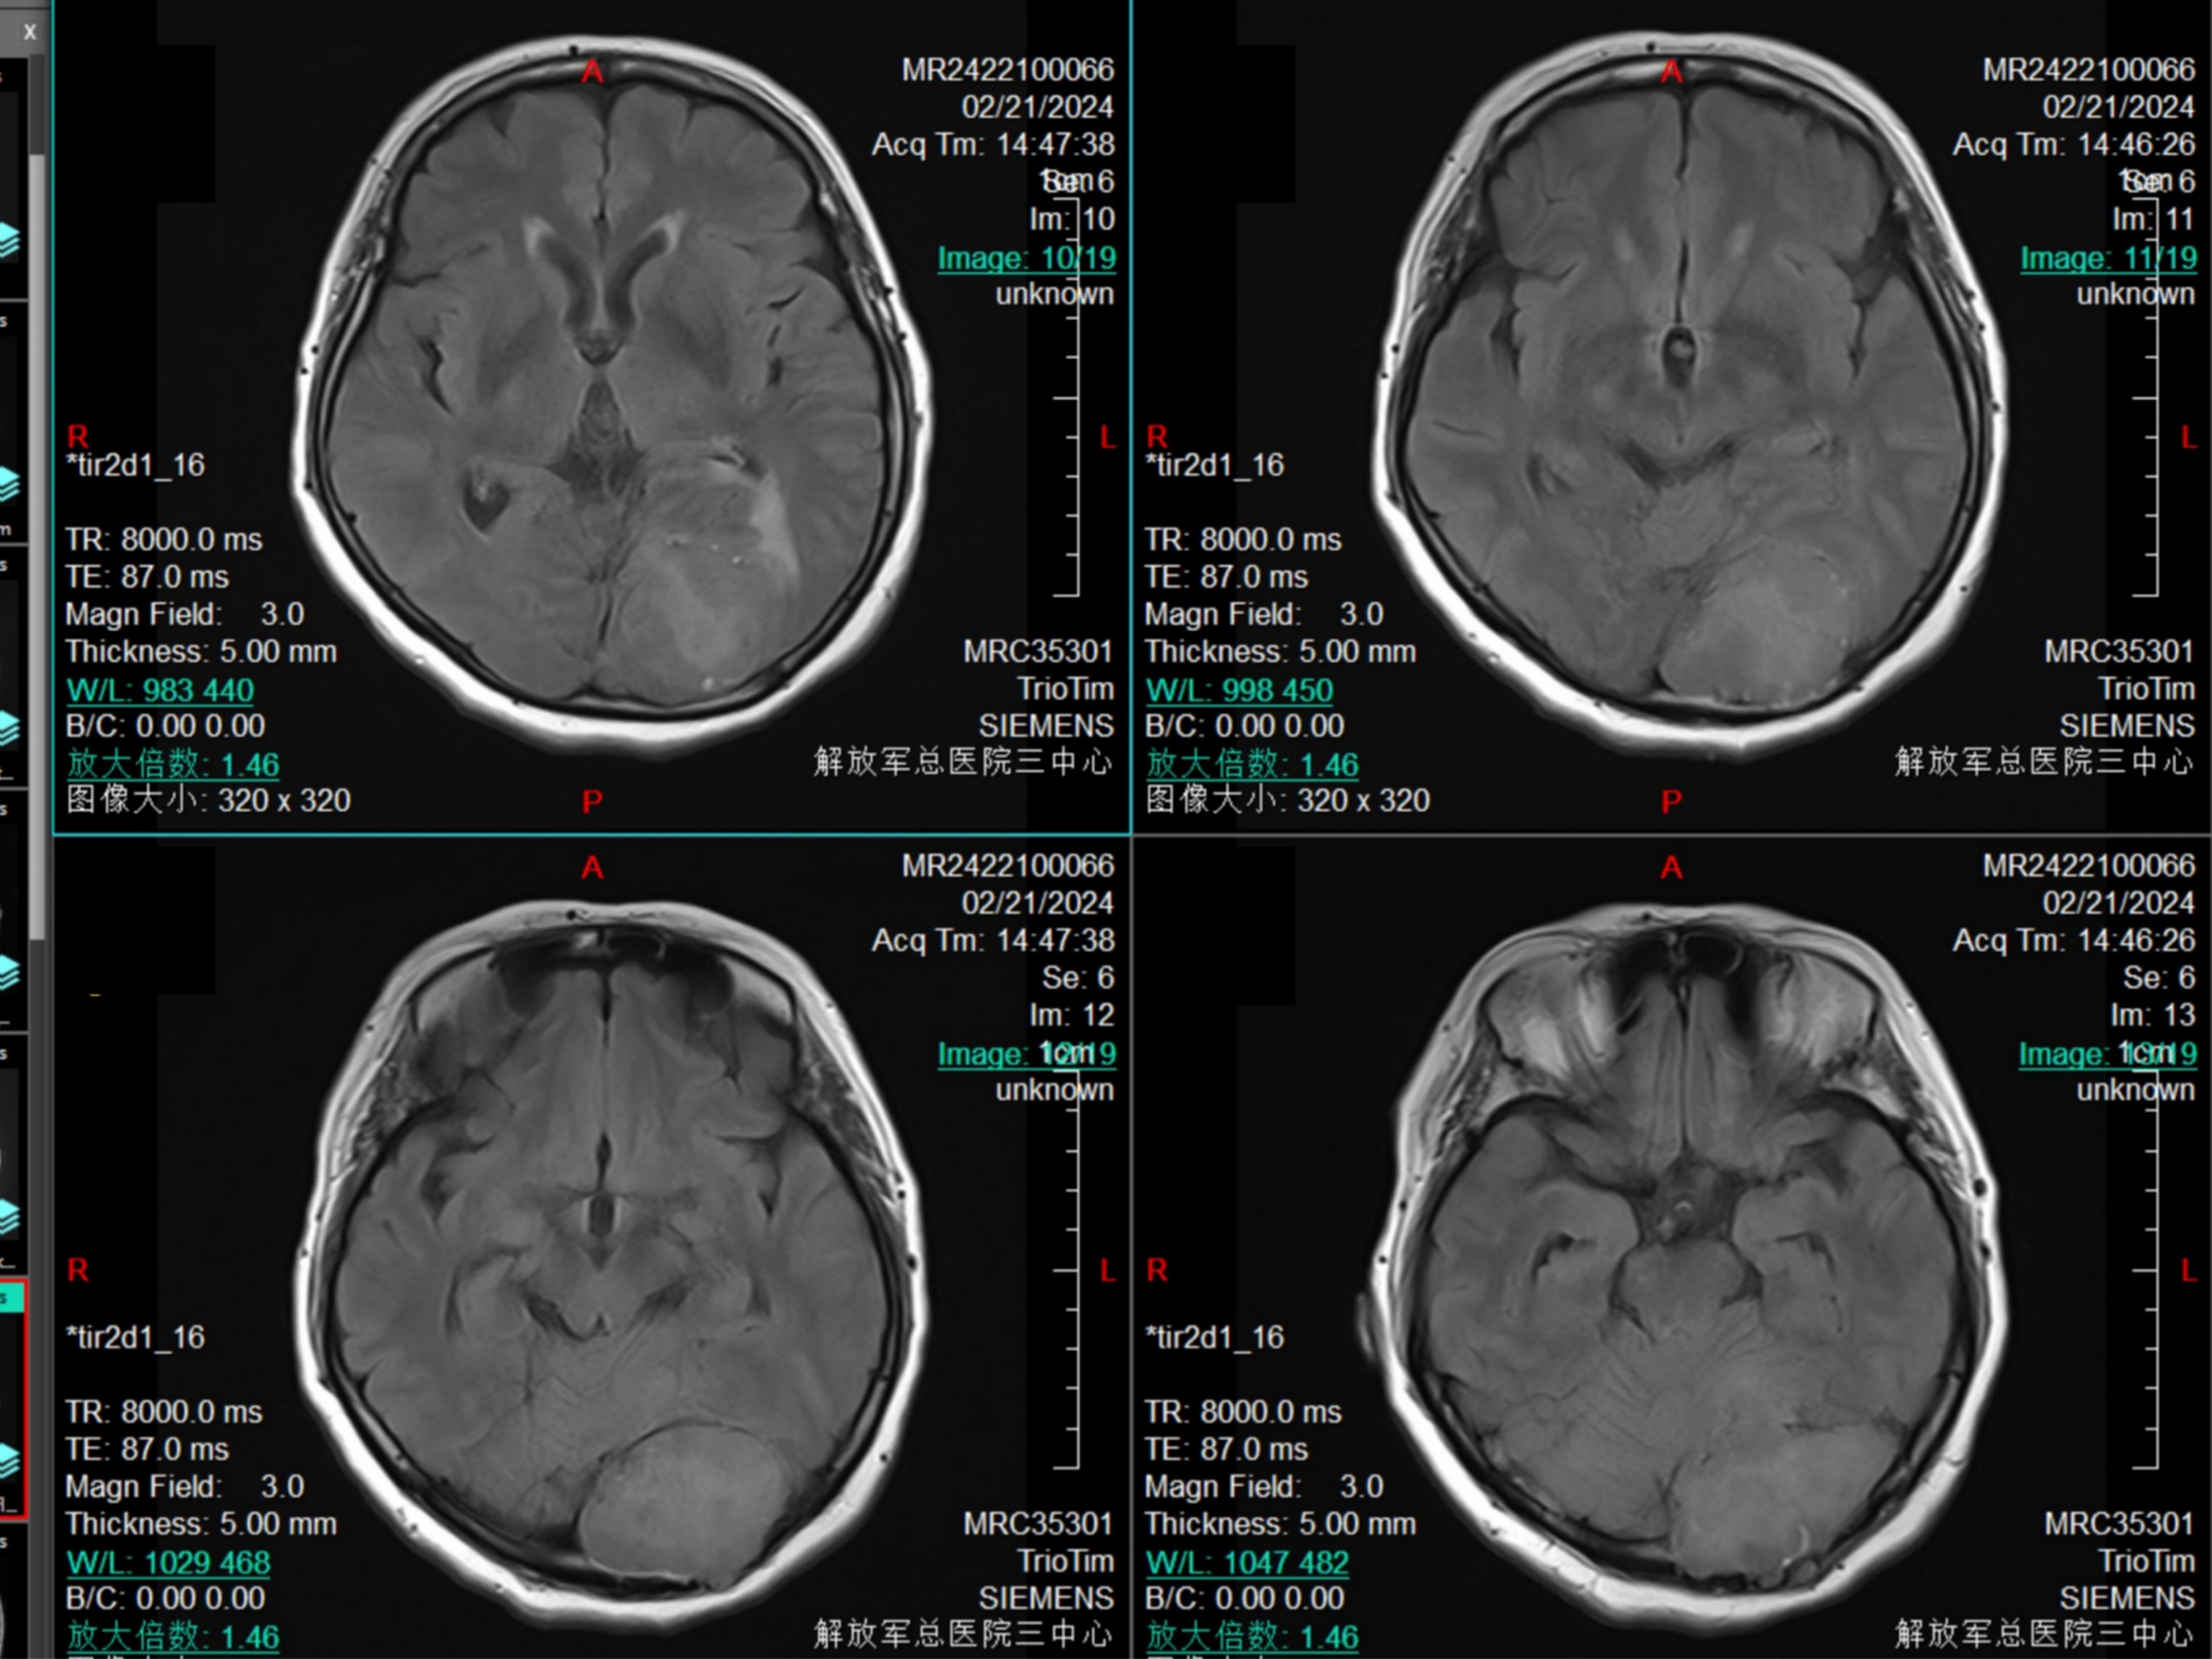

等T1信号

DWI为等信号,有黑色现状结构,考虑为膨胀性生长的小脑幕结构。